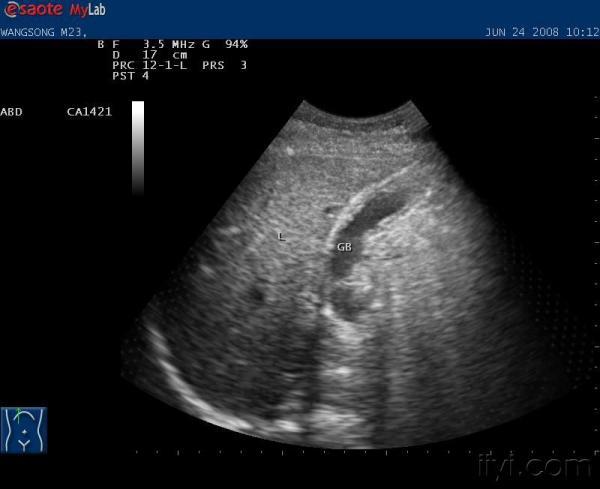

请大家帮助看看这个胆囊有没有问题

年轻男性,23岁,无任何不适症状,体检时发现.(禁食水检查)

超声所见:胆囊大小正常,胆囊壁厚,约4MM,且不光滑。

胆囊壁增厚,胆囊腺肌病?肝质地回声不均匀,是否得过肝炎

慢性胆囊炎